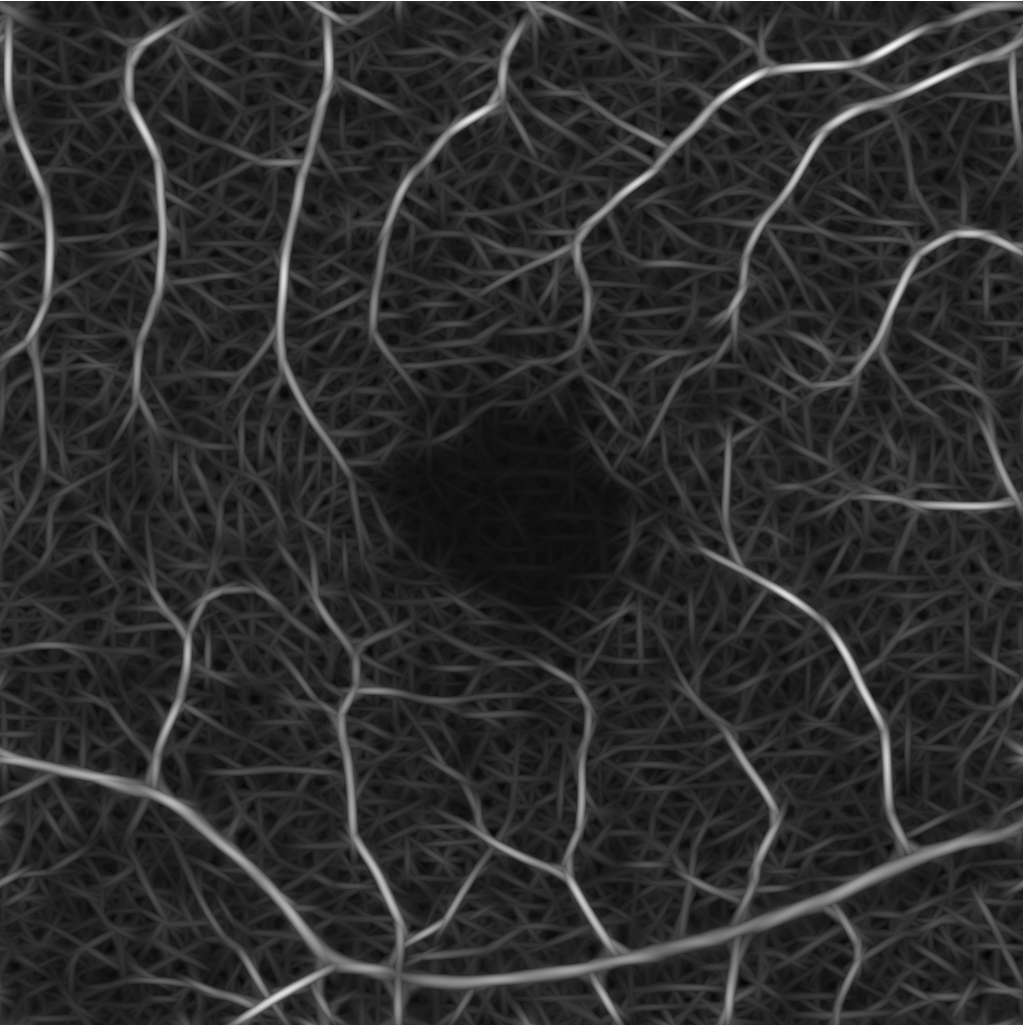

for some chosen frequency ω𝜔\omega, orientation θ𝜃\theta and σ1subscript𝜎1\sigma_{1}, σ2subscript𝜎2\sigma_{2} correspond to the spatial widths of the filter, which is then applied to an image. Here, we choose the parameters as suggested in [19] and use 333 frequency scalings {ωi}i=13superscriptsubscriptsubscript𝜔𝑖𝑖13\{\omega_{i}\}_{i=1}^{3} and 666 orientations {θj}j=16superscriptsubscriptsubscript𝜃𝑗𝑗16\{\theta_{j}\}_{j=1}^{6} to create our Gabor filter bank. The 36=1836183\cdot 6=18 computed Gabor filters are then convolved with the original image Im×n𝐼superscript𝑚𝑛I\in\mathbb{R}^{m\times n} to derive the new image representations in m×nsuperscript𝑚𝑛\mathbb{R}^{m\times n}. Next, for fixed ωisubscript𝜔𝑖\omega_{i}, we take the pixel-wise maximum in the images corresponding to the 666 orientations {θj}j=16superscriptsubscriptsubscript𝜃𝑗𝑗16\{\theta_{j}\}_{j=1}^{6}, leading to 333 images I1,I2,I3subscript𝐼1subscript𝐼2subscript𝐼3I_{1},I_{2},I_{3} with different emphasized frequency ranges, see Figure 1. These new representations are our basis for the further processing.

Figure 1: New image representations are obtained by the convolution of the original image I𝐼I with Gabor filters. The images I1,I2,I3subscript𝐼1subscript𝐼2subscript𝐼3I_{1},I_{2},I_{3} correspond to the 333 chosen frequency ranges defined by {ωi}i=13superscriptsubscriptsubscript𝜔𝑖𝑖13\{\omega_{i}\}_{i=1}^{3}.